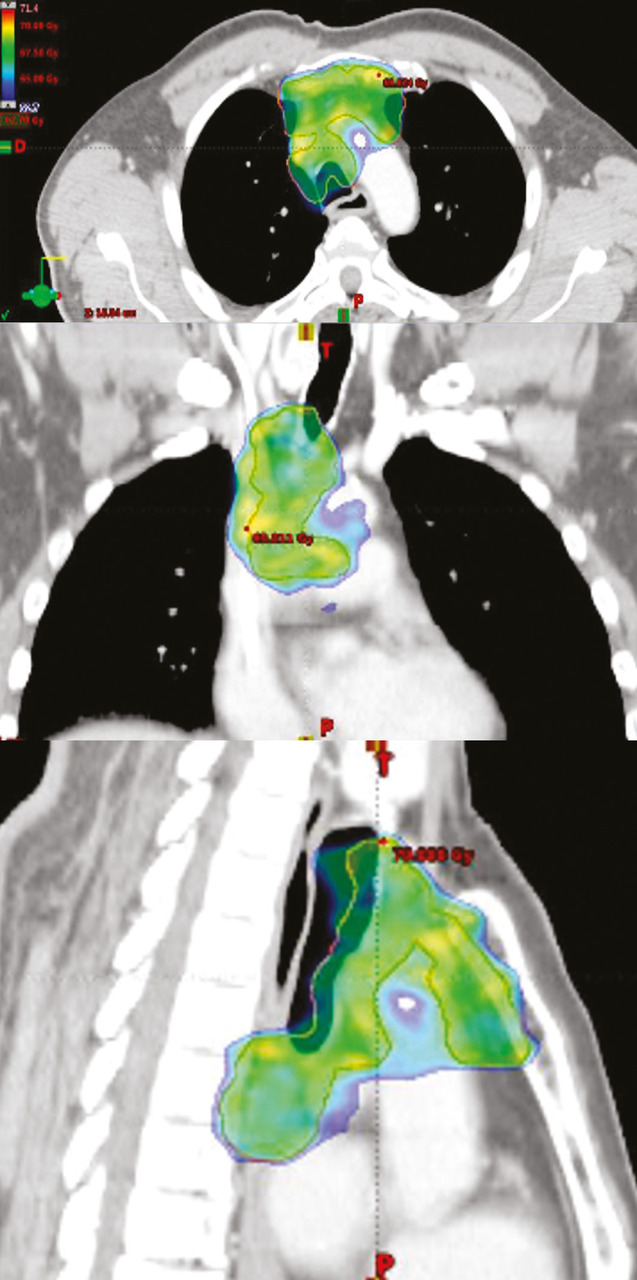

La radiothérapie conformationnelle avec modulation d’intensité (RCMI) – dont il existe plusieurs variantes  : arcthérapie dynamique, tomothérapie – est devenue la technique standard de traitement de la plupart des cancers, notamment en situation curative.14 Elle permet de sculpter la répartition de la dose sur le volume cible (tumeur ou lit tumoral et adénopathies) et ainsi d’épargner les OAR avoisinants (fig. 2). Elle est indissociable d’un contrôle qualité régulier lors du traitement grâce à l’imagerie de contrôle embarquée sur les accélérateurs (imagerie 2D ou 3D scanographique). Si la RCMI est bien sûr utile chez tous les patients, elle prend toute sa place chez la personne âgée, limitant les effets indésirables aigus et tardifs  : diminution très significative de la xérostomie lors des irradiations de la sphère ORL à l’origine de mycoses et de dénutrition d’installation rapide et souvent sévères chez le sujet âgé, diminution de la fréquence et de la sévérité des diarrhées, des rectites et des cystites dans les irradiations abdomino-pelviennes, meilleure protection de la moelle iliaque dans les irradiations pelviennes, ce qui peut être un atout en cas de syndrome myélodysplasique.